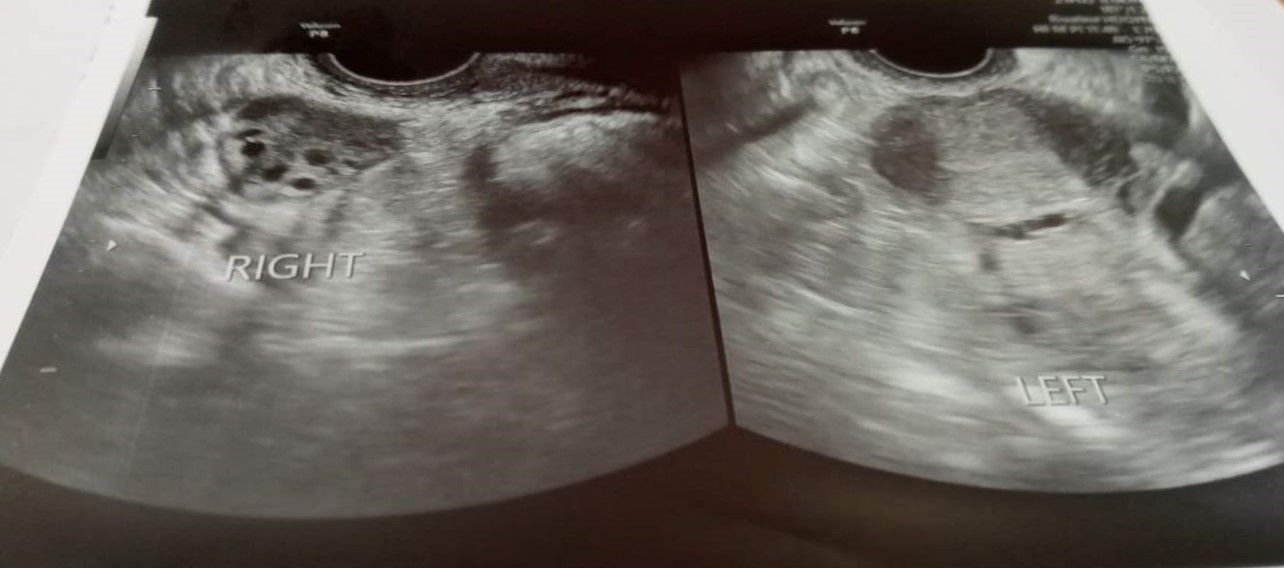

Khoa Nội tổng hợp 1 (Hô hấp – Nội tiết – Bệnh nhiệt đới), Bệnh viện Đa khoa quốc tế Hải Phòng vừa tiếp nhận một bệnh nhân nữ, 33 tuổi, nhập viện vì đường máu cao khó kiểm soát (Glucose máu: 19 mmol/l, HbA1C – chỉ số đường huyết trung bình trong 3 tháng trước đó của bệnh nhân tăng rất cao: 12,5%). Khai thác tiền sử, bệnh nhân bị vô sinh nhiều năm do hội chứng buồng trứng đa nang. Một năm nay bệnh nhân mới phát hiện tiểu đường typ 2. Qua thăm khám thấy bệnh nhân có thể trạng béo (BMI 28,3 kg/m2) ,có dấu hiệu rậm lông, kinh nguyệt không đều, siêu âm thấy buồng trứng nhiều nang nhỏ. Đây là những triệu chứng điển hình của hội chứng buồng trứng đa nang.

Hội chứng buồng trứng đa nang là một hội chứng lâm sàng được đặc trưng bởi béo phì nhẹ, kinh nguyệt không đều hoặc vô kinh và các dấu hiệu thừa androgen như rậm lông, mụn trứng cá…Hầu hết các bệnh nhân có nhiều nang trong buồng trứng. Nguyên nhân gây ra buồng trứng đa nang được cho là do kháng Insulin – là nguyên nhân gây ra bệnh tiểu đường typ 2. Những người mắc hội chứng buồng trứng đa nang có nguy cơ mắc bệnh tiểu đường typ 2 gấp 4 – 8 lần so với phụ nữ không mắc hội chứng buồng trứng đa nang.